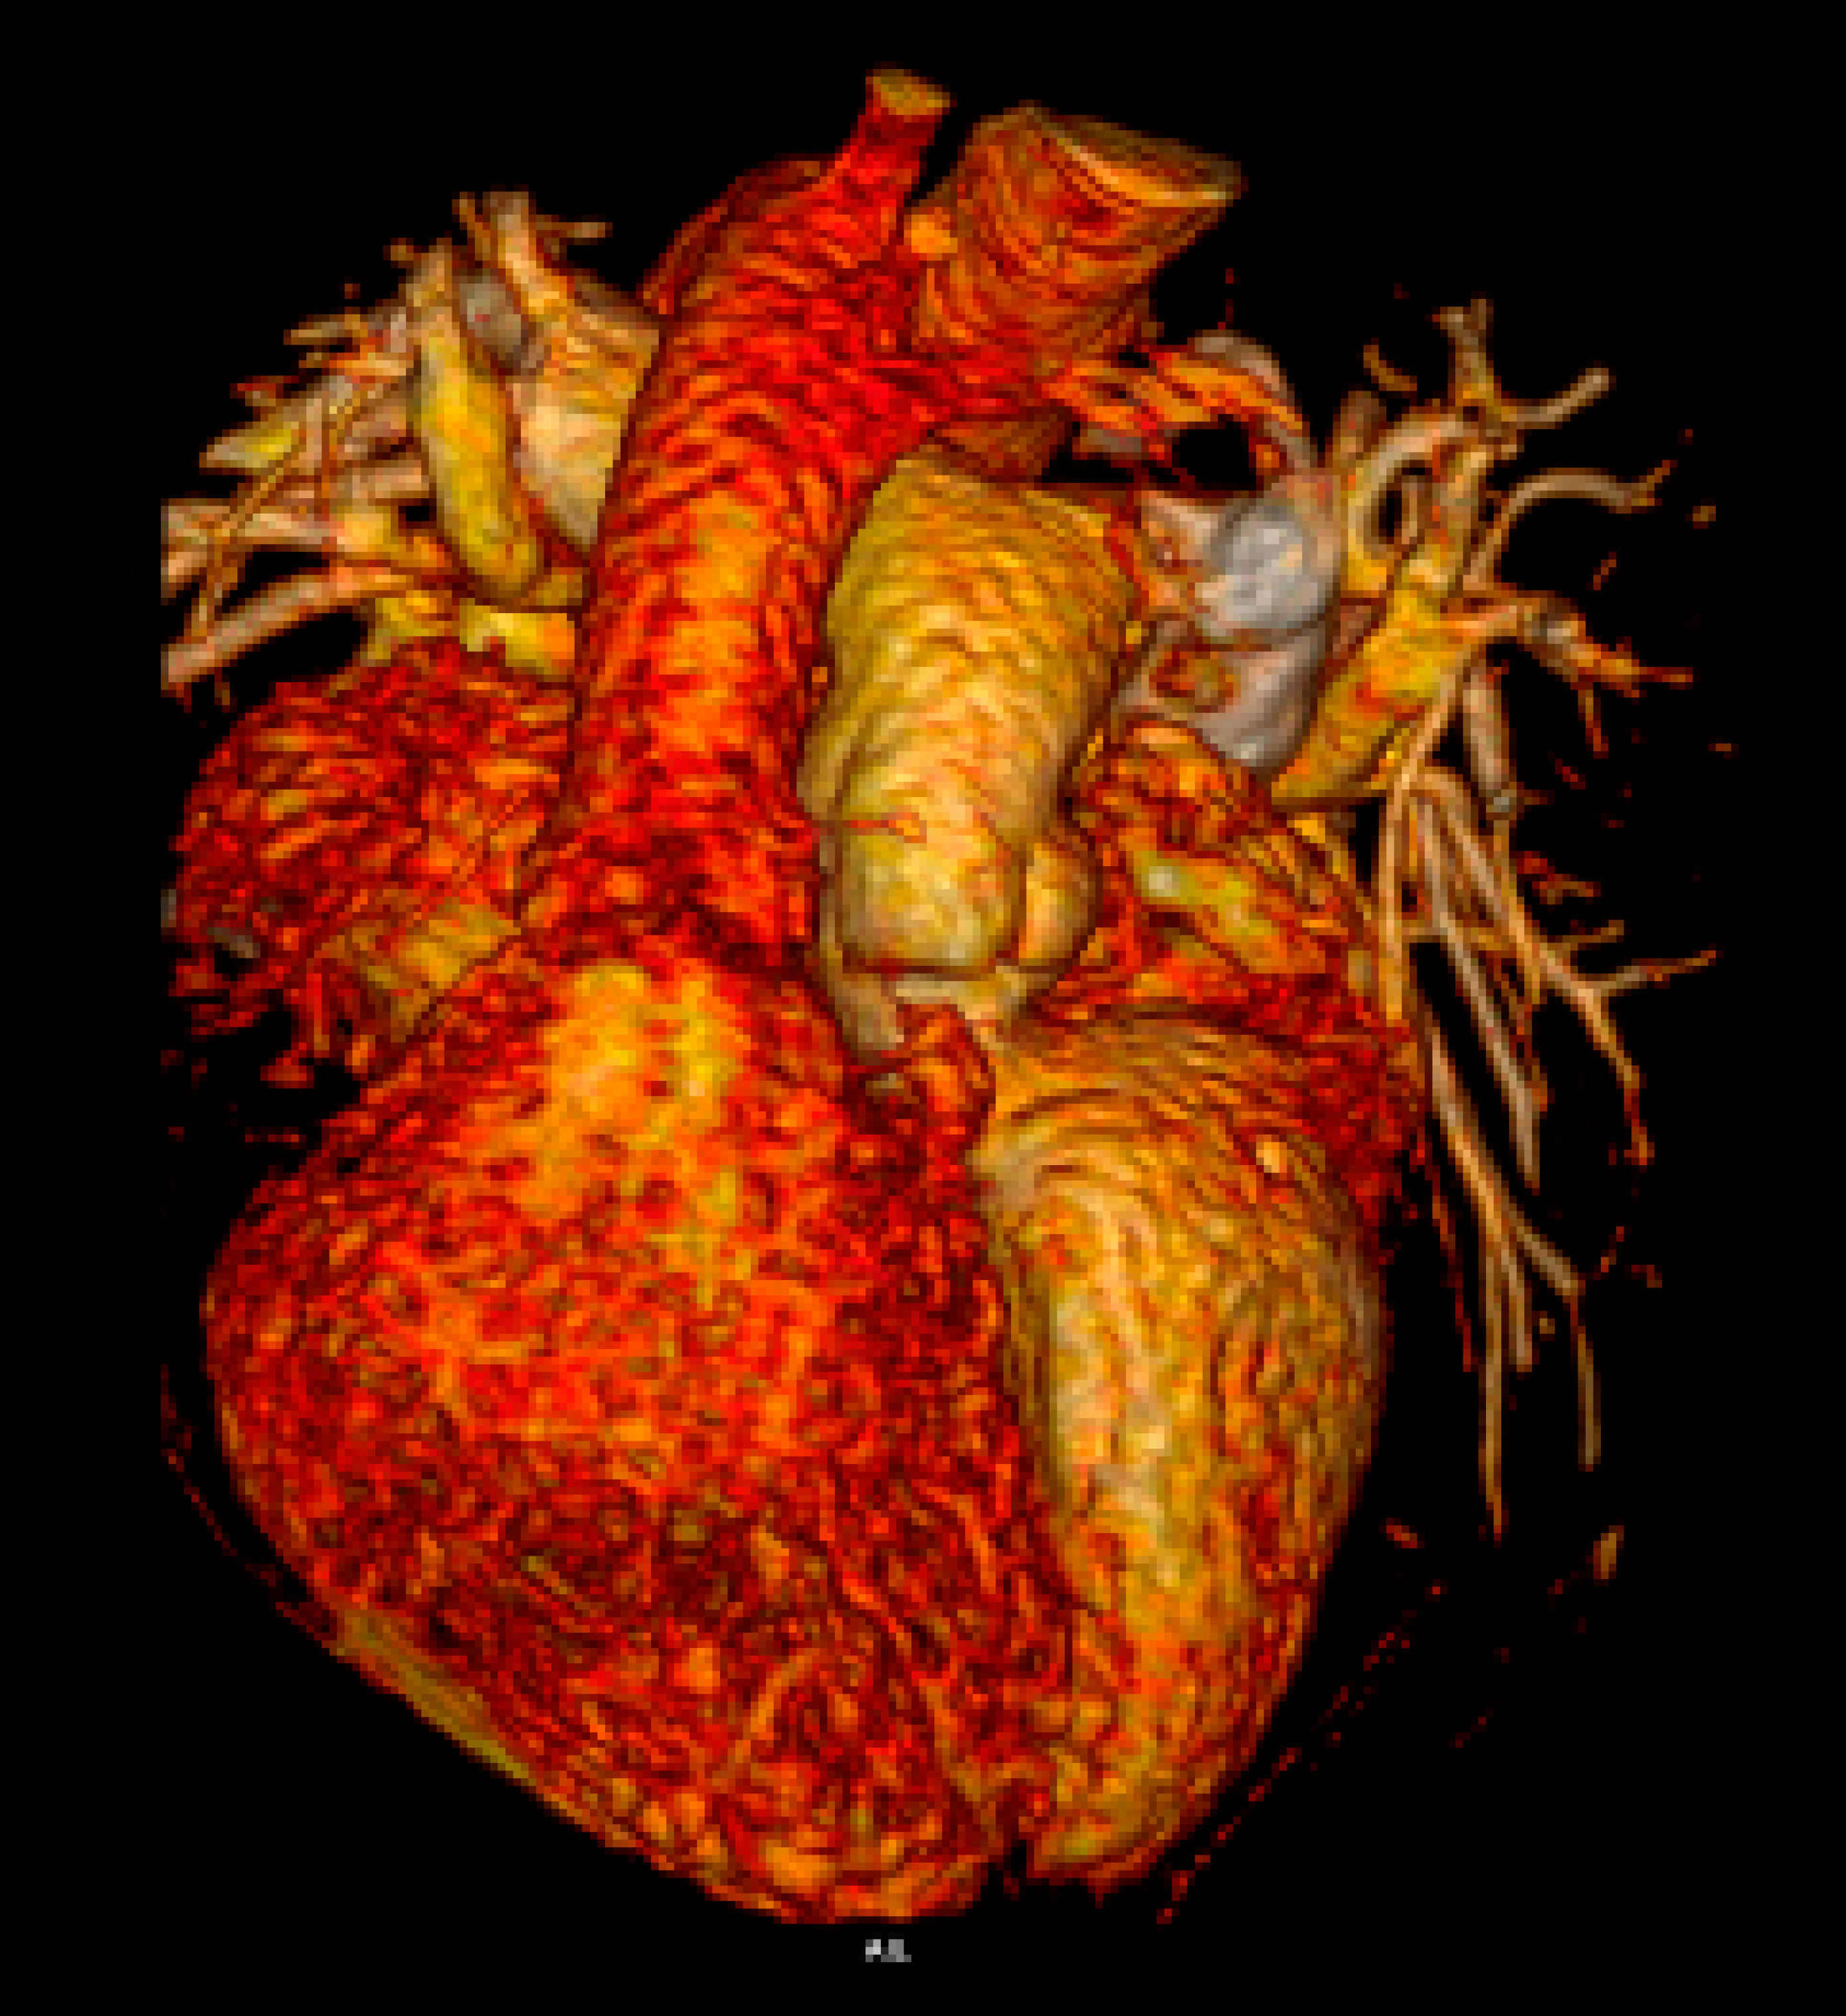

Bloqueo auriculoventricular completo en un paciente adulto con transposición congénitamente corregida de grandes arterias aisladas y situs inversus

La transposición congénitamente corregida de grandes arterias (TccGA) es una cardiopatía congénita poco común. Muchos pacientes permanecen asintomáticos cuando no hay lesiones cardiacas presentes (TccGA aislada). En la TccGA, el sistema de conducción auriculoventricular puede ser anormal, lo que resulta en una disfunción progresiva y, finalmente, en un bloqueo auriculoventricular (BAV) completo. En la TccGA con situs inversus, la vía de conducción se asemeja a un tracto normal, pero el nódulo auriculoventricular se ubica posteriormente. En comparación con el situs solitus, el BAV completo espontáneo es poco común en pacientes con TccGA con situs inversus. Se presenta el caso de una mujer de 40 años sin enfermedades previas ni con antecedentes familiares o personales de cardiopatías que presentó pérdida de conciencia. Al ingreso, el electrocardiograma reveló bradicardia, BAV completo e hipertrofia del ventrículo derecho. Estudios de imagen cardiaca detectaron una TccGA aislada con situs inversus y levocardia. El monitoreo Holter reveló BAV completo intermitente. Las pruebas de esfuerzo demostraron incompetencia cronotrópica. Se le implantó un marcapasos epicárdico y la paciente fue dada de alta asintomática. Tras dos años de seguimiento permaneció asintomática. Este caso ilustra la importancia de imagen cardiovascular para definir la anatomía cardiaca, descartar otras cardiopatías congénitas y facilitar la terapia de estimulación cardiaca en cardiopatías congénitas complejas. Los pacientes con cardiopatías congénitas deben ser tratados por un equipo multidisciplinario con experiencia en estimulación cardiaca permanente.

Figura 1